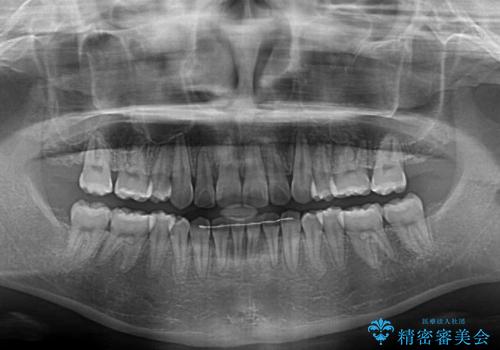

- 八重歯やデコボコをインビザラインで治療したいとのことで来院された患者様です。

インビザライン単体で治療を行うには叢生が強いと判断されたため、事前にワイヤー装置で抜歯矯正を行い、ある程度改善してからインビザラインにて仕上げていくこととしました。